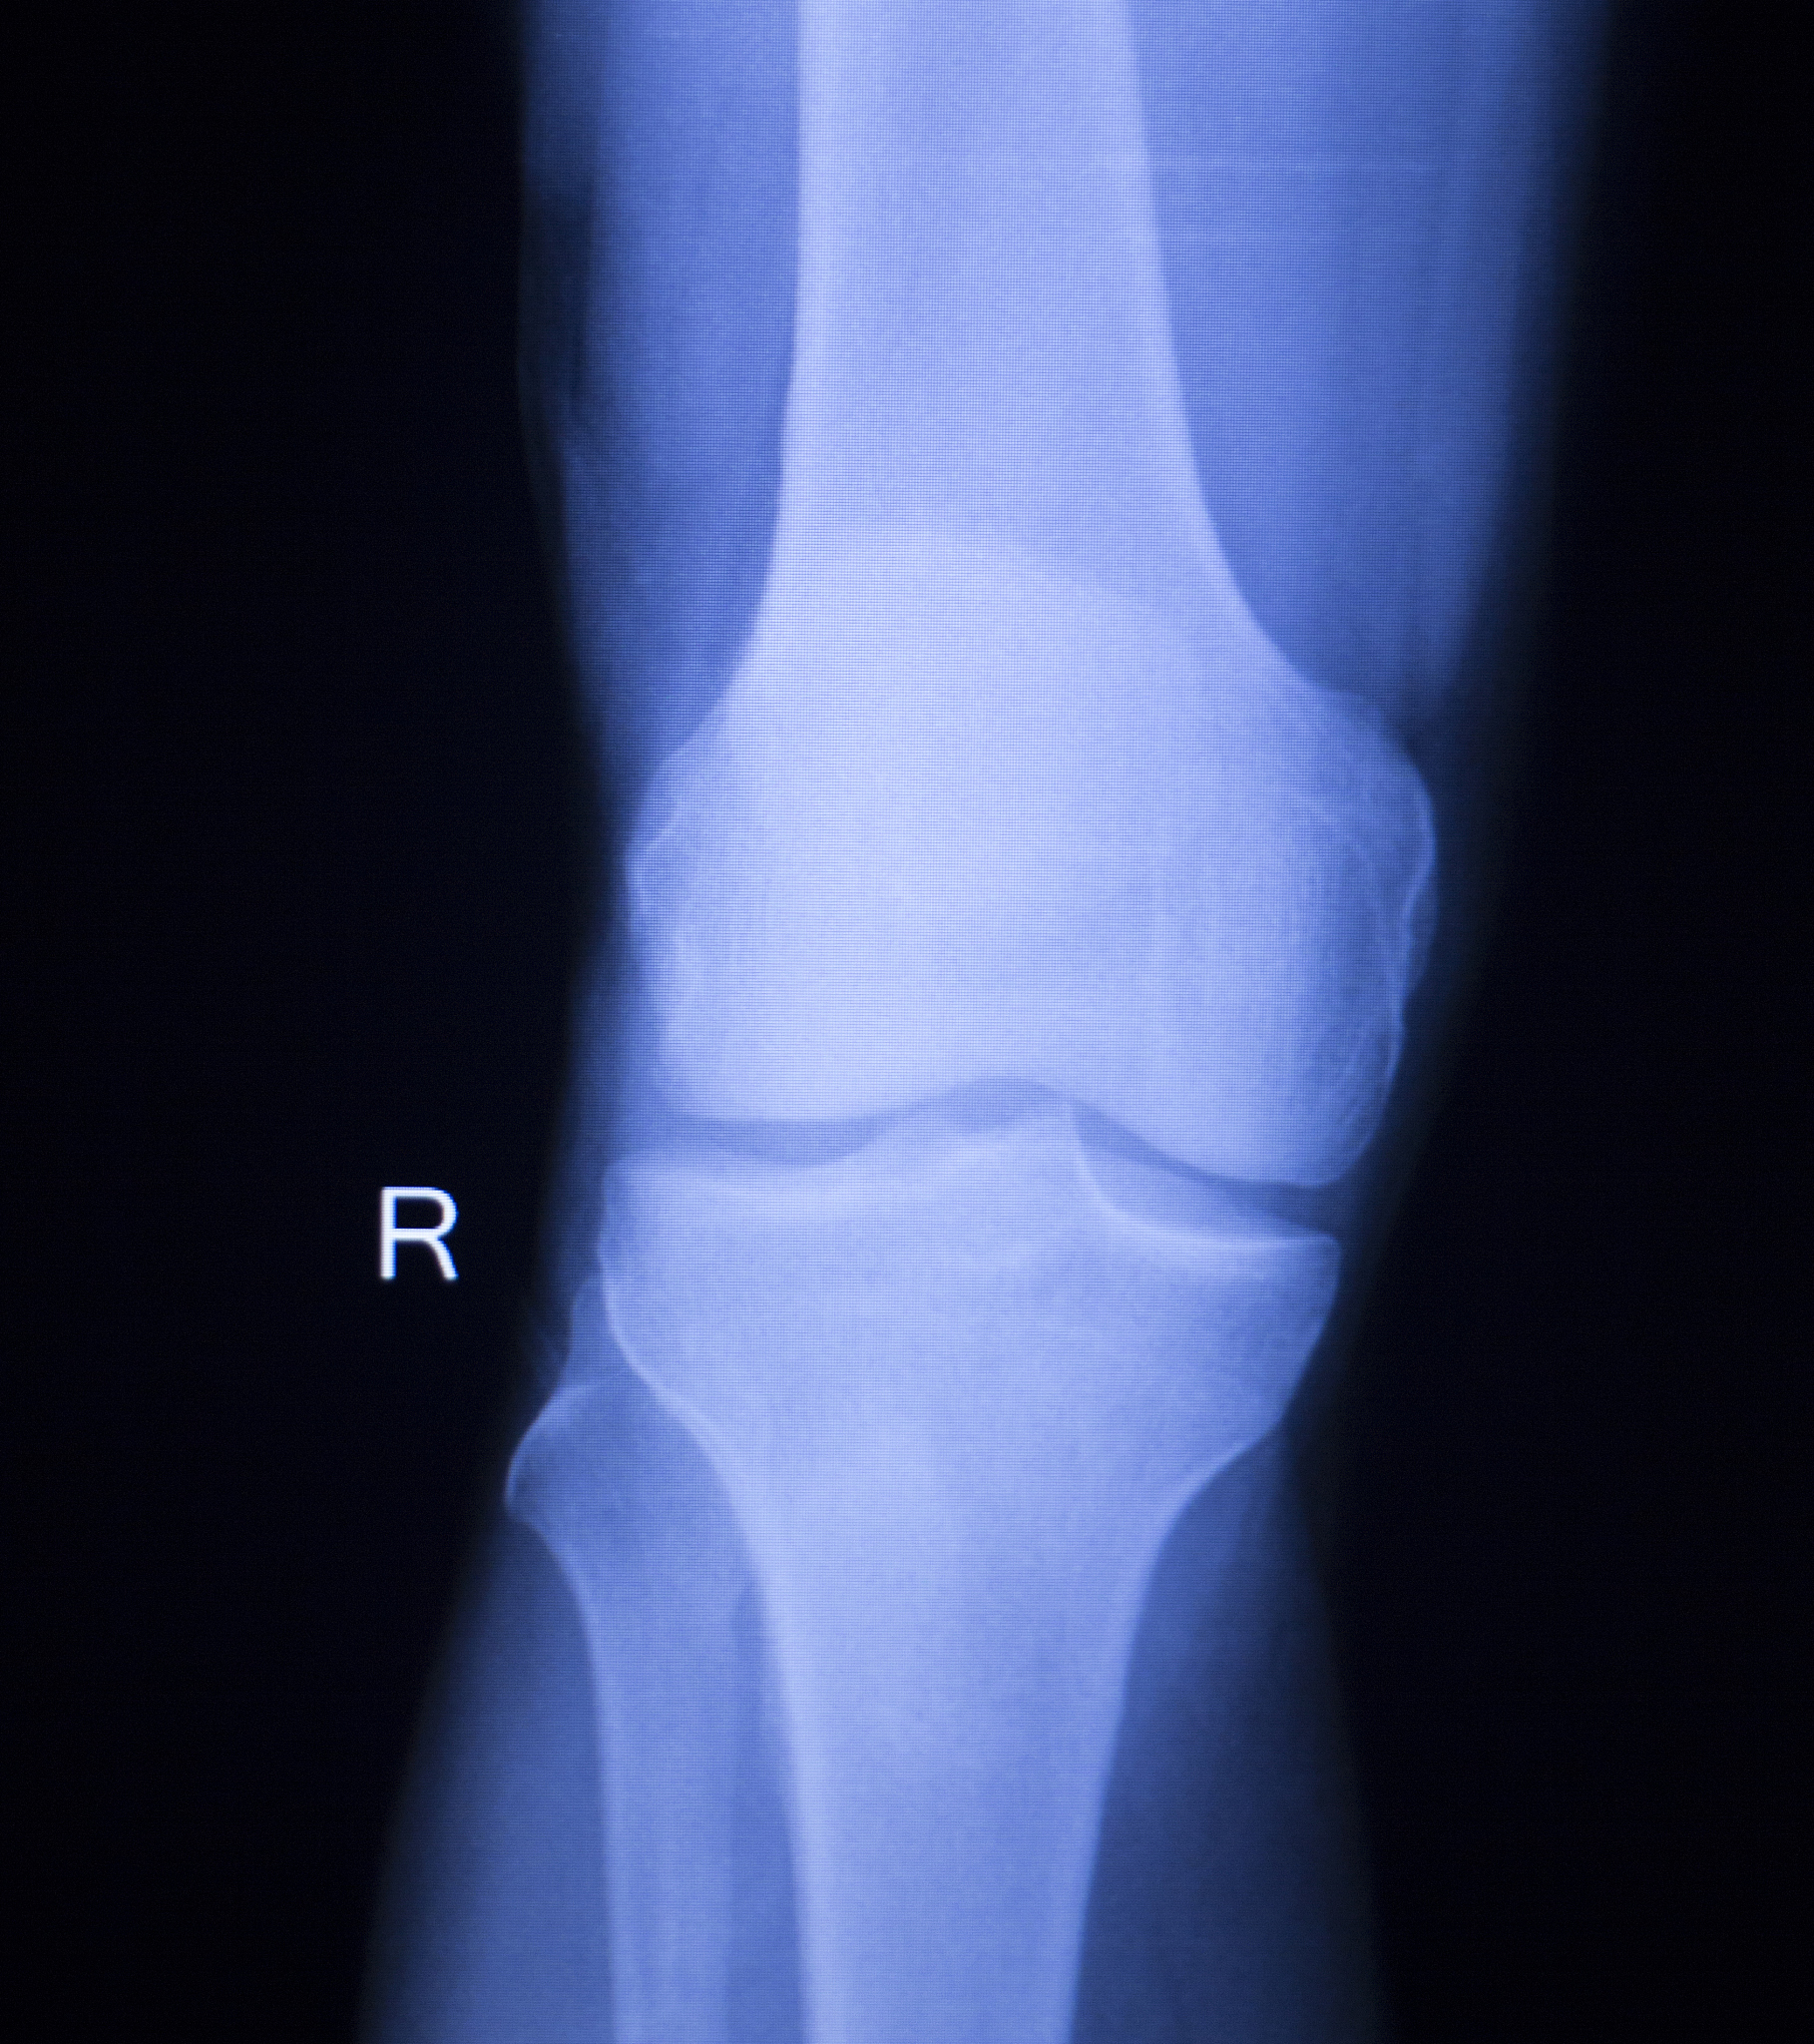

左股骨粗隆间骨折的诊断

• X光检查: 明确骨折部位、类型和程度。* CT扫描: 更清晰地显示骨折情况,辅助制定手术方案。